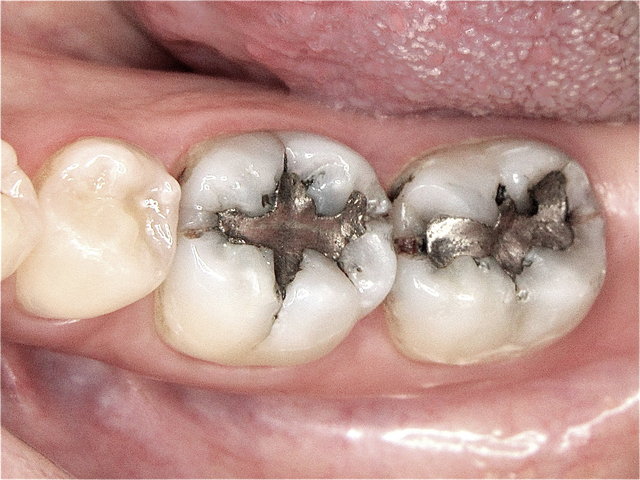

Undichte dunkel verfärbte Amalgam-Füllungen ...

Composit-Füllungen by CLINICDENT ✓